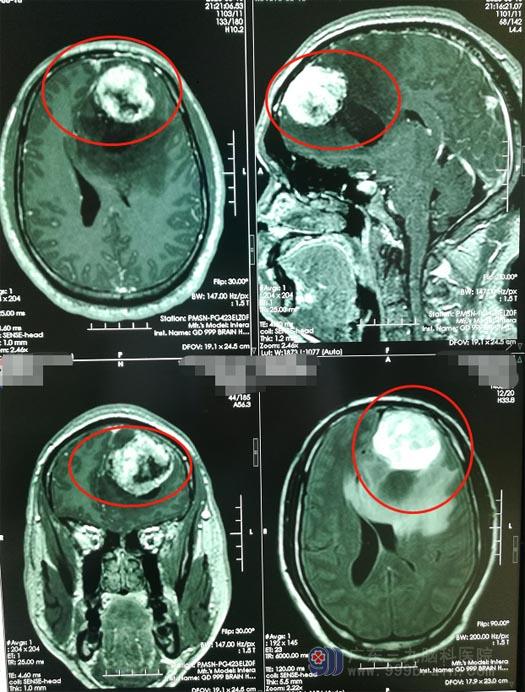

近10天来,陈先生每隔1-2天就会发作一次,并伴有呃逆及恶心感,随着晕厥的发作频率增加,家人意识到了问题的严重性。当地医院头部CT检查提示双额叶及胼胝体区病变存在,考虑是脑部肿瘤。广东三九脑科医院的头颅MR显示:左额叶占位,考虑肿瘤性病变。

医院副院长、神经外五科主任鲁明查房后指示:陈先生颅内占位考虑肿瘤性病变,病变体积大,并且临近功能区,水肿严重,需尽快手术切除。额叶是脑功能区,稍有不慎,可导致肢体偏瘫,言语功能障碍等。经过慎重的术前讨论后,决定采用术中唤醒麻醉,利用神经电生理技术精确定位脑重要功能区并探询病变与功能区的关系,最大限度切除肿瘤并保留功能区。术中,见肿瘤的血供丰富,术中冰冻病理提示脑膜瘤,显微镜下将肿瘤全切。